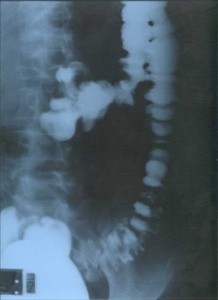

La presenza di diverticoli nell’intestino spesso non dà alcun sintomo particolare e la maggior parte delle persone se ne accorge solo in seguito ad esami (colonscopia o clisma opaco – fig. 2 – o colon tac – fig. 1) condotti per altre ragioni.